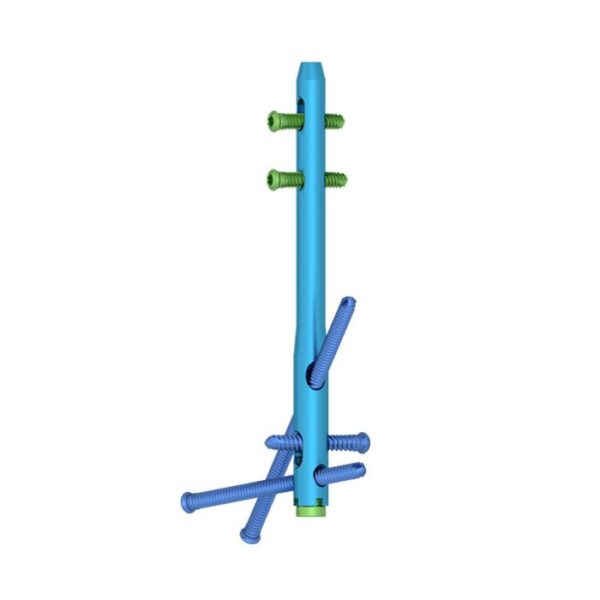

Clavo de artrodesis de tobillo:

- Proporcione diferentes diámetros y longitudes para más opciones clínicas.

- Los diferentes colores son fáciles de distinguir.

Orificios de bloqueo estáticos y dinámicos:

- Proporcione orificios de bloqueo estáticos y dinámicos en el proximal.

Tornillos distales para cepillado múltiple que cruzan los orificios de bloqueo:

- Fijación de articulaciones cruzadas para mejorar la estabilidad de la fusión.

- El tornillo se inserta oblicuamente en la apófisis anterior del calcáneo o en la articulación calcáneo-cuboidea para mejorar la fuerza y la estabilidad de extracción.

Tornillos de bloqueo:

- Diseño de ranura autorroscante para facilitar la inserción.

- Rebajo Torxdrive del diseño de la cabeza del tornillo para reducir el tornillo suelto.

- Agujeros proximales dinámicos y estáticos con tornillo de bloqueo de 5.0 mm.

- Tres orificios transversales distales coinciden con el tornillo de bloqueo de 6,0 mm.

Tapa final:

- Evita que los tejidos blandos crezcan.